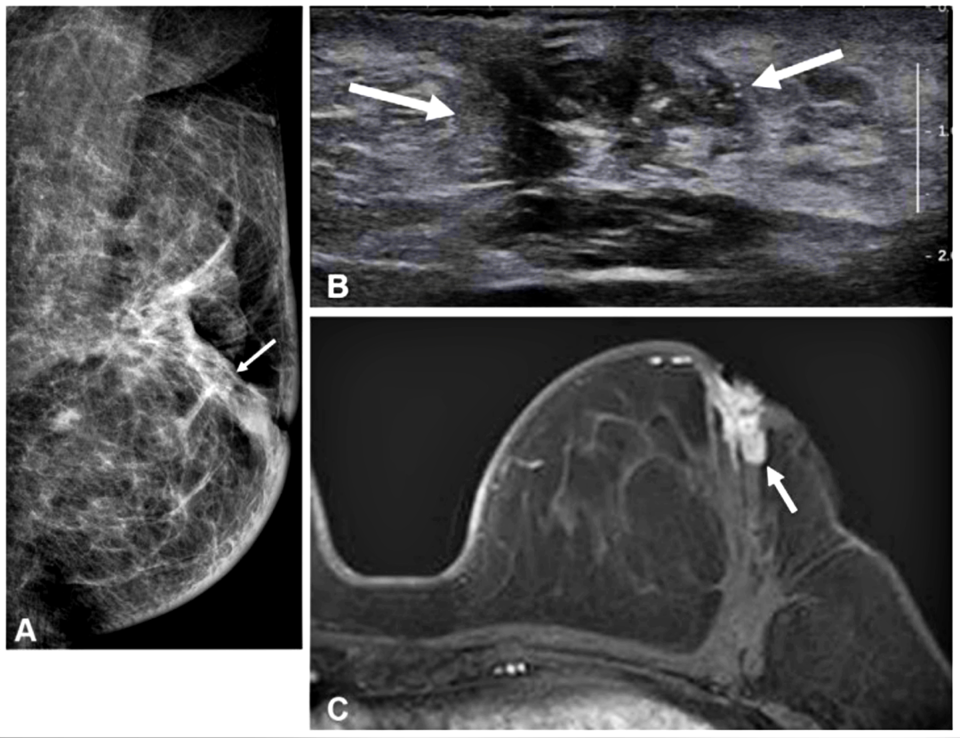

【서울 = 서울뉴스통신】 최정인 기자 = 50세 이하 유방암 환자가 수술 전에 MRI(자기공명영상) 검사를 받을 경우 암 재발 위험이 크게 줄어드는 것으로 나타났다. 특히 재발률이 높고 예후가 불량한 ‘호르몬 수용체 음성 유방암’ 환자에서 그 효과가 두드러져, 맞춤형 치료 전략 수립에 중요한 근거가 될 것으로 평가된다.

서울대병원 영상의학과 하수민·연희라 교수, 유방내분비외과 김홍규 교수 연구팀은 2011년부터 2017년까지 수술을 받은 50세 미만 유방암 환자 4,414명을 대상으로 수술 전 MRI 시행 여부에 따른 장기 예후를 비교한 결과를 5일 발표했다. 연구는 환자들의 수술 후 평균 7.7년간 추적 관찰을 통해 진행됐다.

그 결과, 전체 재발률은 두 그룹 간 큰 차이가 없었지만, 수술한 쪽 유방 내 국소 재발률은 MRI군이 1.6%로, 비MRI군(3.3%)보다 절반 이하로 낮았다. 특히 호르몬 수용체 음성 환자군에서는 효과가 더욱 뚜렷해, MRI군의 전체 재발 위험은 8.2%로 비MRI군(20.7%) 대비 60% 이상 감소했다. 반면 호르몬 수용체 양성 환자군에서는 유의한 차이가 관찰되지 않았다.

연구팀은 “재발 위험이 높고 호르몬 치료 반응이 낮은 호르몬 수용체 음성 유방암 환자의 경우, 수술 전 MRI 검사가 종양의 위치와 범위를 정확히 파악해 정밀한 수술 계획을 세우는 데 도움을 줄 수 있다”며 “이는 장기적으로 재발을 예방하고 환자의 생존율을 높이는 효과로 이어질 수 있다”고 설명했다.